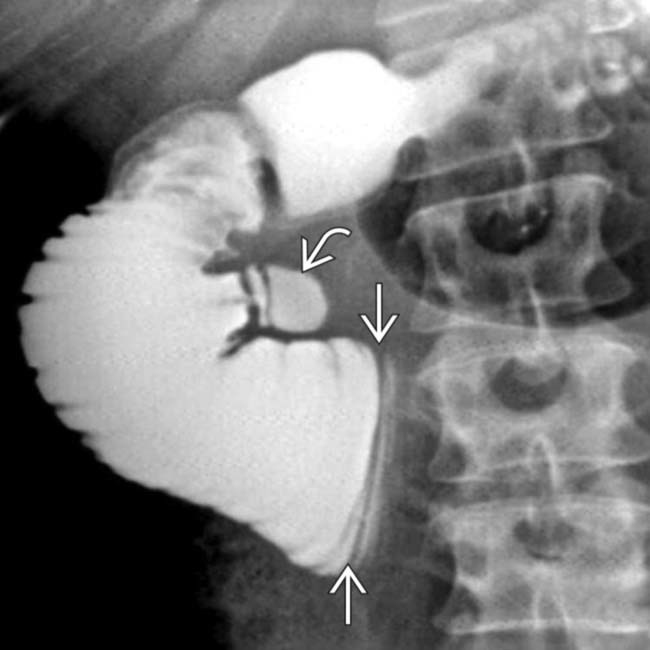

Menetrier’s disease

Classic appearance with massively enlarged folds in the body without abnormality in the antrum.

This condition is characterised by hypertrophy of gastric glands, achlorhydria and hypoproteinaemia. Loss of protein from the hyperplastic mucosa into the gastric lumen results in a protein-losing enteropathy, and may produce disabling symptoms. The disease is characterised by markedly enlarged, often bizarre gastric folds most prominent in the proximal stomach and along the greater curvature.